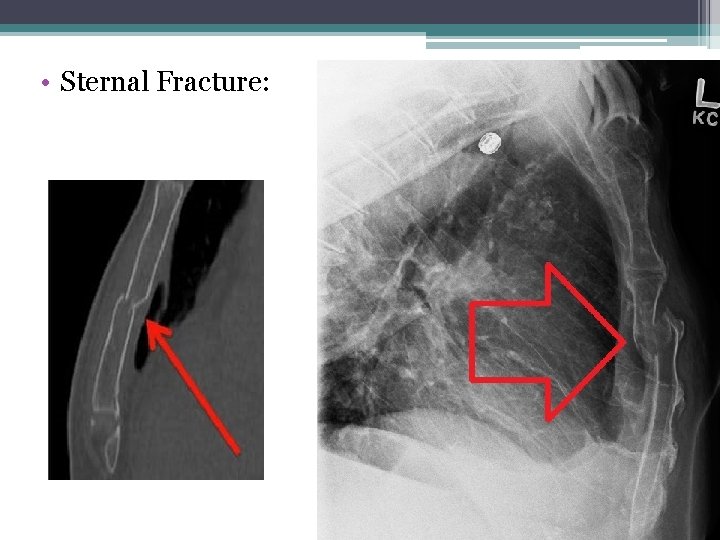

• Sternal Fracture: